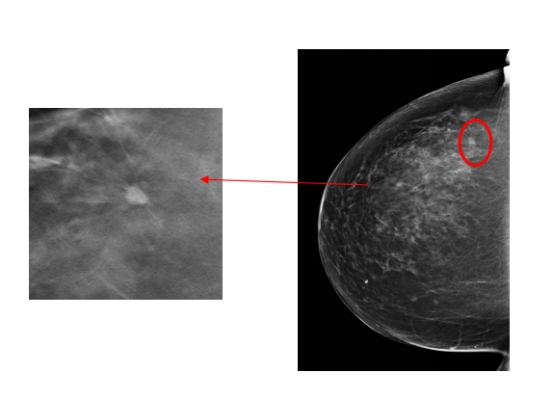

ac米兰官网中文网站一院放射科主任陈颖教授介绍,由于李女士比较年轻,属于致密型乳腺,常规的乳腺钼靶摄片未发现明显的肿块,仅显示双乳增生及良性钙化。数字化乳腺断层摄影断层图像显示左乳外上象限长了一个5mm的结节,经放射线科钼靶室医生会诊发现,该结节有很大可能性是恶性的乳腺癌,因此建议李女士做活检或者入院手术治疗。术中冰冻切片发现该结节是乳腺原位癌,因此医生为她制定了保乳手术的治疗方案,目前正在康复中。术后,李女士特意打电话感谢放射线科的医生们帮助她及早地发现了这个病灶。

2020年末ac米兰官网中文网站一院放射线科引进(HOLOGIC)数字化断层乳腺机,与传统的数字化钼靶乳腺机相比,能够最大限度地减少乳腺组织重叠,尤其是对年轻东方女性的致密型乳腺能够明显提高病灶检出率,大大降低了假阳性率及假阴性率。